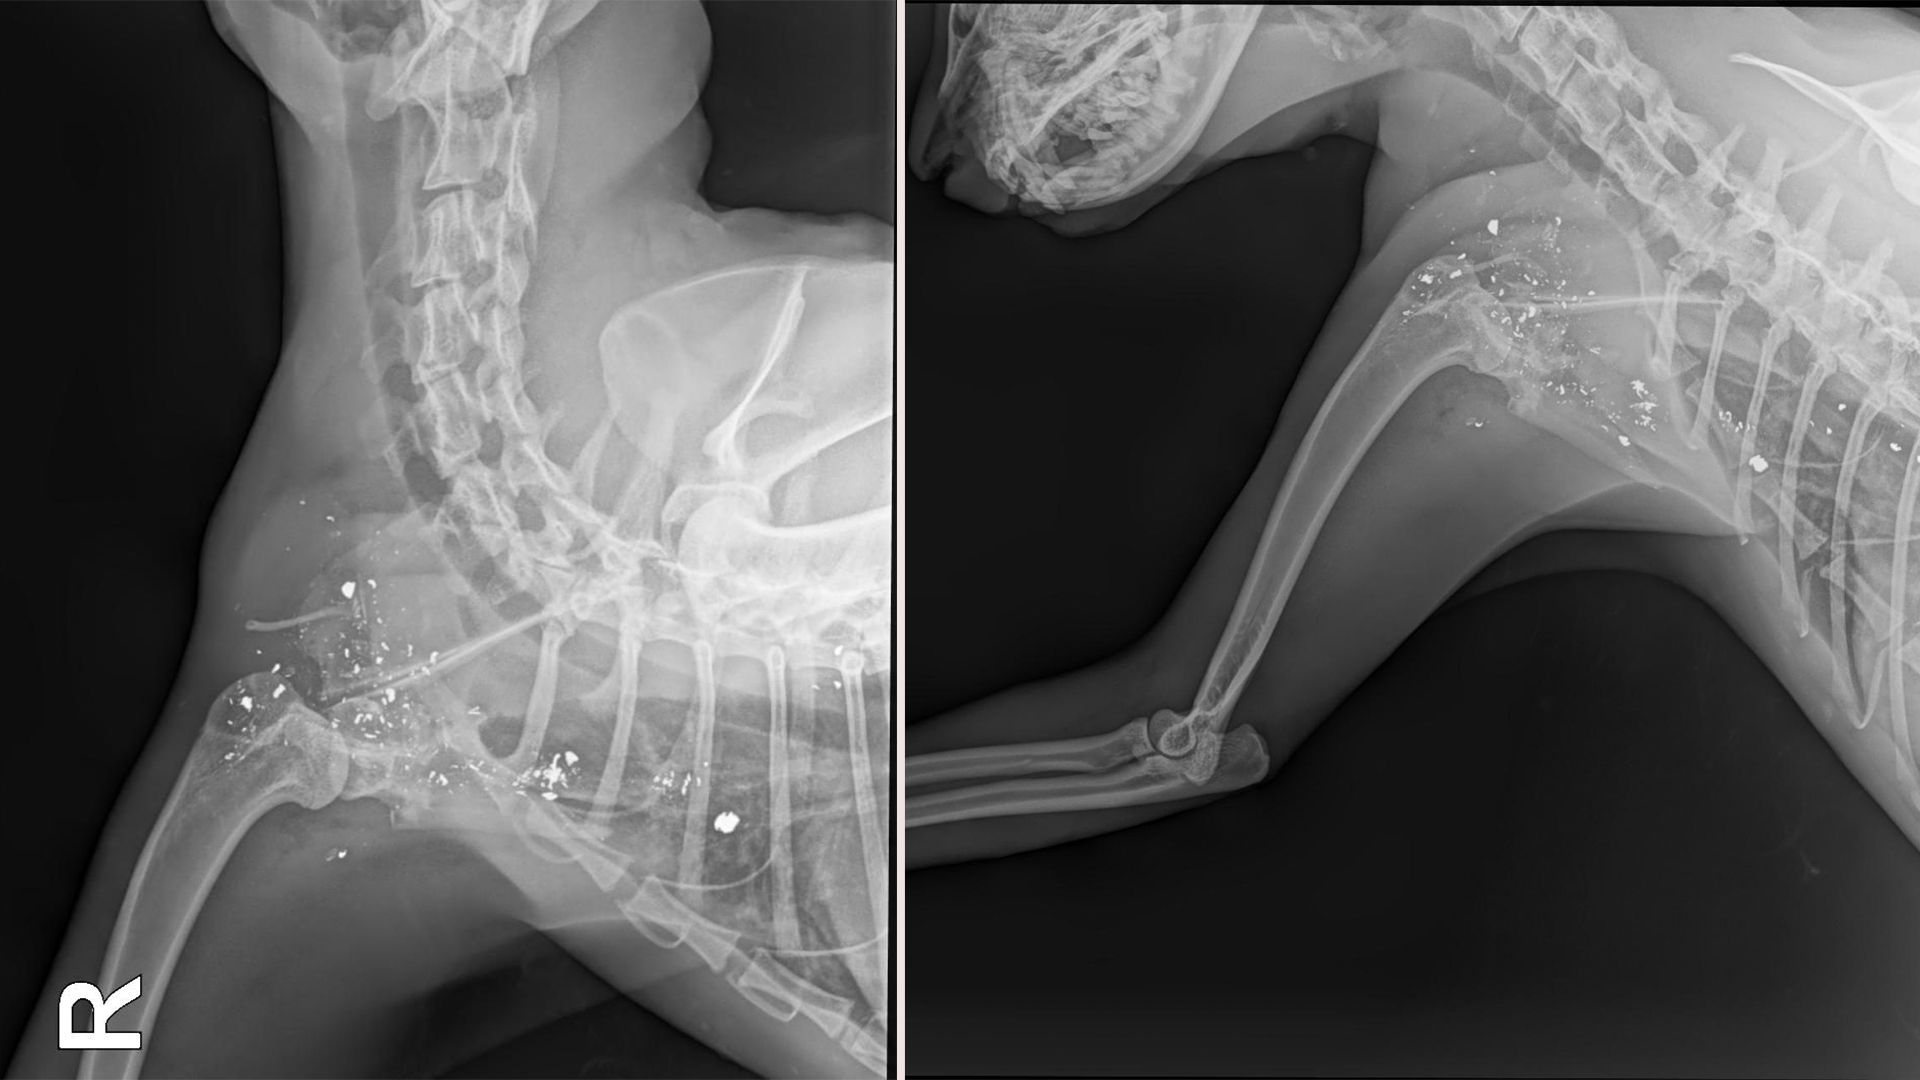

Leider sind viele Blei-Fragmente inoperabel.

©Tierparadies Schabenreith

Die Tierärztin brauchte nicht lange, um der Wurzel allen Übels auf den Grund zu gehen, denn der kleine Katzenkörper war voller Schrotkugeln. Die Projektilfragmente, von denen viele entlang der Wirbelsäule sitzen, sind größtenteils nicht operabel und haben erhebliche neurologische Schäden verursacht. Pengasius leidet unter starken motorischen Einschränkungen und zeigt aufgrund seiner Schmerzen ein sehr aggressives Verhalten.